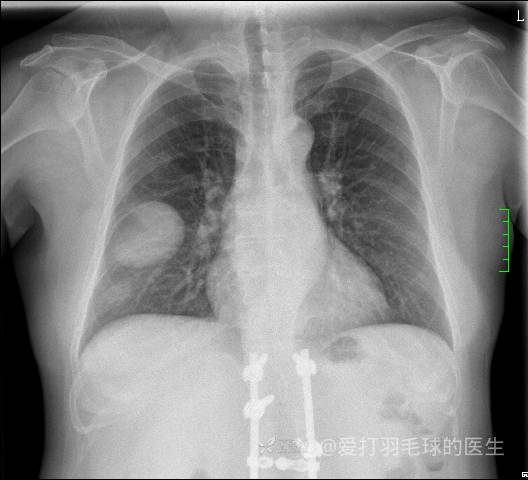

中年女性,全身多处“疙瘩”,长了切,切了又长,分型是关键,已公布结果。

患者性别:女

患者年龄:44岁

主诉:患者因反复右侧腰痛伴右下肢麻木2年余入院。

简要病史:自诉右甲状腺功能亢进症多年,规律服药,平素多有心悸、胸闷、活动后明显。既往腰椎椎管内肿瘤切除术。